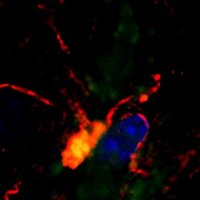

Preprint from the lab SLU Department of Pharmacology & Physiology SLU Research investigating the role of lipid metabolism in lymphatic endothelial cells👇👇 Insulin regulates lymphatic endothelial function via palmitoylation biorxiv.org/content/10.110…